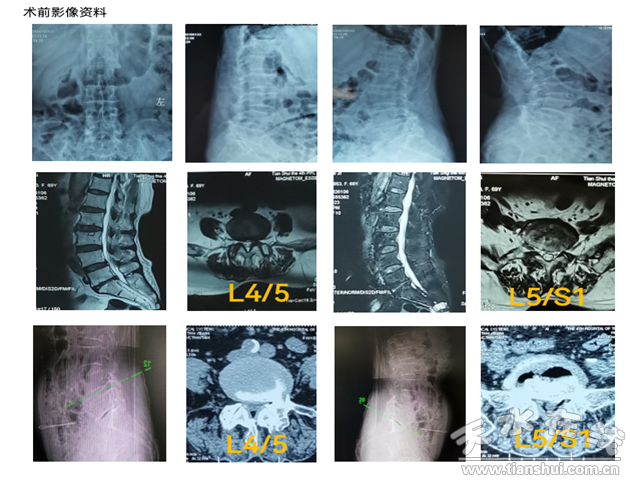

患者70歲,女性,主訴腰痛伴左下肢疼痛麻木1年,加重2月余。患者行走200米后出現(xiàn)腰痛及左下肢疼痛麻木,必須下蹲休息數(shù)分鐘后才能繼續(xù)行走,近2月來進(jìn)行性加重,近一周疼痛加重?zé)o法下地行走。X線、CT及MRI 顯示:腰4/5、L5/S1節(jié)段椎管狹窄,神經(jīng)根和硬膜囊受壓,在我市多家醫(yī)院保守治療無效,嚴(yán)重影響患者生活質(zhì)量。

患者住院后科室副主任韋瑋通過詢問病史,仔細(xì)體格檢查,結(jié)合影像學(xué)檢查,和患者及家屬充分交流溝通,經(jīng)甘肅省中醫(yī)院脊柱微創(chuàng)骨科王想福主任醫(yī)師會診后,確定該患者適合在全麻下行UBE手術(shù)。因患者影像學(xué)表現(xiàn)雙節(jié)段狹窄,但患者臨床表現(xiàn)是L5神經(jīng)根受壓體征,術(shù)前先進(jìn)行左側(cè)L5神經(jīng)根阻滯,患者左下肢疼痛即刻緩解約80%,明確責(zé)任間隙后,隨后在UBE下行L4/5椎管減壓術(shù),歷經(jīng)1小時手術(shù)順利完成,麻醉清醒后患者左下肢疼痛消失,活動良好。術(shù)后第二日即佩戴腰圍下地活動,無疼痛不適。